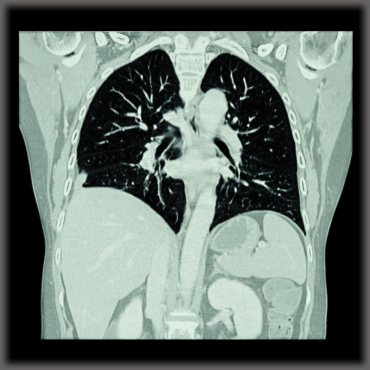

Researchers Advance Pulmonary Embolism Diagnosis Through Computed Tomography

Written by Patricia Silva, PhD

Researchers atLeiden University Medical Center.in The Netherlands recently published in the journal Diagnostic and Interventional Radiology a review on the value of computed tomography (CT) as a diagnostic tool for pulmonary embolism. The study is entitled “The role of computed tomography in the diagnosis of acute and chronic pulmonary embolism.”